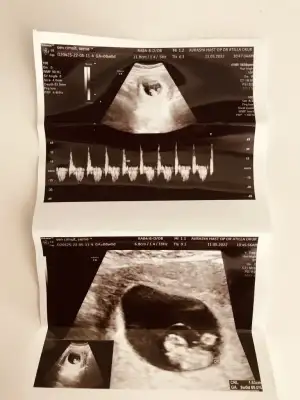

8 haftalık burda güzel teyzeleri çok merak ediyorum bana da yorum yapın annem 3 sene tüp bebek deneyip bana hamile kaldı şimdi cinsiyetimi öğrenip hasırlık yapmak istiyor

Eklentiler

• 068C4138-1445-4676-9B9A-4BA91C51D59A.webp

068C4138-1445-4676-9B9A-4BA91C51D59A.webp

38,4 KB · Görüntüleme: 77